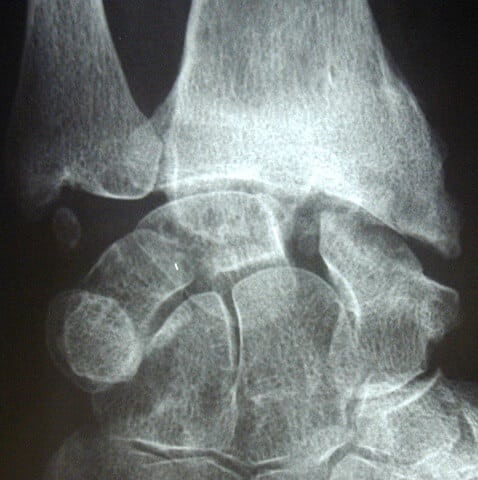

entorse ligament poignet rupture

Diastasis important par rupture ligamentaire complète du ligament scapho lunaire